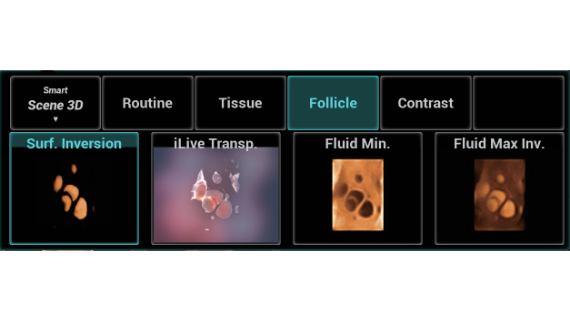

Nuewa I9? ??? ???? ?? ??? ?? ??? ???? ?? ??? ???? ???? ??? ?????. ??? ??? ??? ?? ????? ?? ???? ???? ???? ???? ??? ???? ??? ??? ???? ??? ???? ??? ?? ?????.